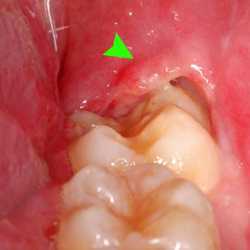

Inicio Especialidades Cirurgia